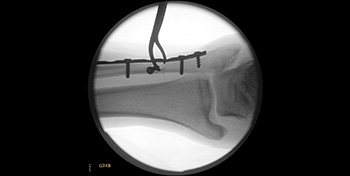

- Day 0 – Fracture reduction using surgical instruments and plate and screws

- Day 0 – With the use of arthroscopy, small bone fragments were identified floating inside the joint that were removed.